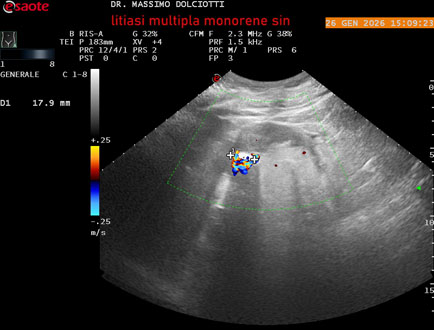

Data inserimento: 29/01/2026

Ecografia del: 26/01/2025

Strumento: Esaote MyLab Eight

Sonda: Conevx Multifrequenza 1-8 MHz

Età Paziente: M 78 anni

Motivazione dell'esame: follow up di litiasi al rene sinistro, in paziente sottoposto a nefrectomia destra.

Commento all'esame: le immagini ed il video documentano il rene sinistro in sede, di ecostruttura disomogenea per evidenza di multiple formazioni litiasiche al pielone superiore, delle dimensioni di 15,9 mm, al pielone medio di 17,5 mm e al pielone inferiore di 18,9 mm e morfovolumetria normale, con diametro bipolare di 115 (v.n. 90-120 mm) x 54 mm e parenchima renale dello spessore di 17 mm ( v.n. > 13 mm).

Conclusioni: litiasi multipla del monorene sinistro (multiple lithiasis of the left solitary kidney).

In collaborazione: Dr.ssa Marica Manfredi - Ancona, Dr. Ilir Qose - Ancona

Presentazione: Dr. Massimo Dolciotti - Ancona

Elaborazione digitale: Andrea Dini - Ancona